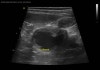

초음파 검사

수술전 복부 초음파검사 / 출처: 라온동물메디컬센터

초음파 검사에서 자궁 내부에 염증성 내용물이 차 있는 소견이 확인되었습니다.